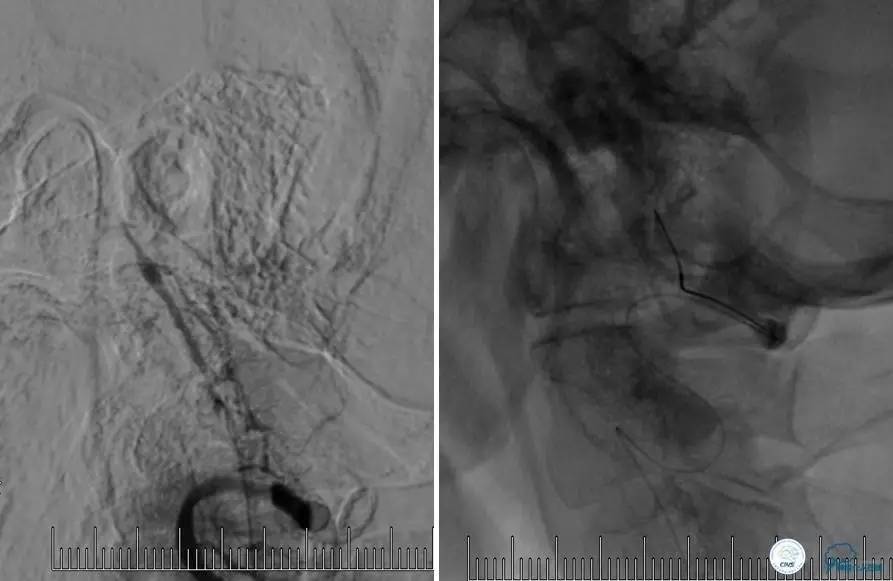

造影评价血管、判断闭塞段,微导丝小心穿过闭塞段,微导管造影,交换技术,球囊扩张,Enterprise支架。在后扩张时导丝刺破M3段血管,蛛网膜下腔出血(SAH)。

微导管进入破裂血管,栓塞弹簧圈1枚,出血停止,结束手术。继续双抗,术后2天肌力2级,神经功能恢复明显加快。